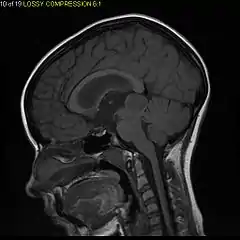

- Sagittal T1-weighted MRI showing a well-circumscribed hypointense mass in the tectum (presumably a tectal plate glioma). These lesions are a distinct subset of pilocytic astrocytoma which present with hydrocephalus typically in 6 to 10 year-olds and are rarely progressive lesions. When imaging is characteristic, a biopsy is usually not performed because of the risks to adjacent structures, often shunting to relieve intracranial pressure is the only treatment required.